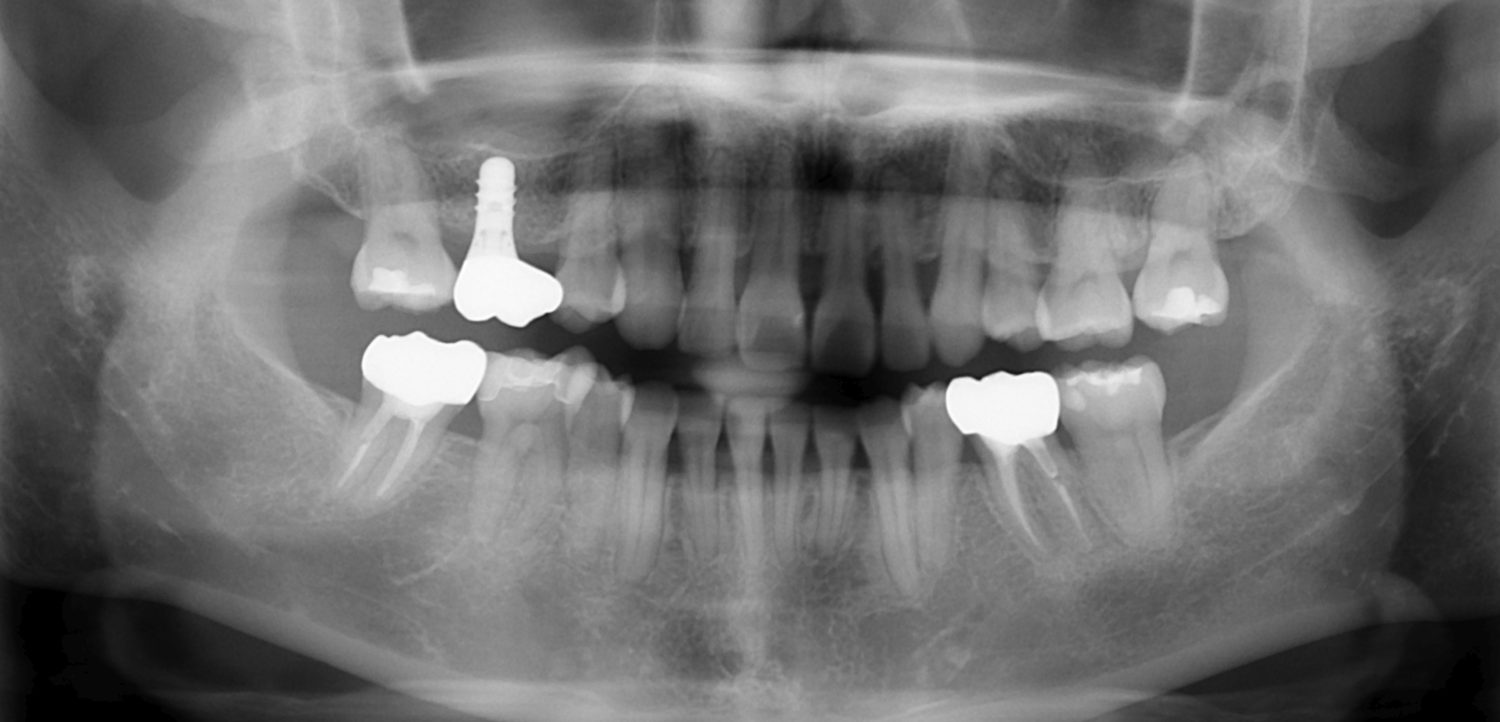

| 主訴 | 20代女性 矯正治療希望。治療途中の歯もあるので治したい。左顎関節が痛い。 |

| 治療内容 | 矯正治療を行いました。 |

| 治療費 | 1,400,000円(税込み) |

| 治療期間 | 3年(矯正治療期間 2年半) |

| 治療回数 | 40回 |

| 想定されたリスク | 顎骨の変形があったので、全身麻酔下による外科処置が必要になり、身体的、精神的負担が増す可能性がありました。 清掃状況によっては矯正中にむし歯が発生するリスクがありました。 |